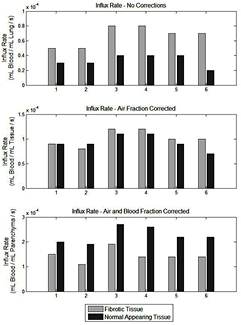

Figure 1 displays the fibrotic (HD) and normal appearing (LD) Patlak derived influx rate constant ( ) for the NC, AFC and ABC cases for all six patients. It can be seen that in all patients the HD regions have a higher

) for the NC, AFC and ABC cases for all six patients. It can be seen that in all patients the HD regions have a higher  than that of the LD region in the NC case (p = 0.01). After AFC, the regions become comparable with a p value of 0.35 and after ABC, the LD regions are significantly increased with respect to the HD regions (p = 0.01). Figure 2 is the SUV equivalent to figure 1 where it can be seen that the trend is similar to the

than that of the LD region in the NC case (p = 0.01). After AFC, the regions become comparable with a p value of 0.35 and after ABC, the LD regions are significantly increased with respect to the HD regions (p = 0.01). Figure 2 is the SUV equivalent to figure 1 where it can be seen that the trend is similar to the  case with the HD regions appearing significantly higher than the LD regions in the NC case (p = 0.0001), approximately equivalent after AFC (p = 0.092) and significantly lower in the ABC case (p = 0.0001).

case with the HD regions appearing significantly higher than the LD regions in the NC case (p = 0.0001), approximately equivalent after AFC (p = 0.092) and significantly lower in the ABC case (p = 0.0001).

Figure 1. Bar graphs displaying the difference in Ki in fibrotic (light grey bars) and normal (dark grey bars) appearing regions determined from the mean of the HDMask and LDMask (with >5% fractional parenchyma volume threshold) over the Ki Patlak parametric images for all analysed patients. In the top chart, no corrections have been applied, the middle chart displays the values following AFC and the bottom chart is after ABC. Note that the influx rate appears higher in fibrotic regions when compared to the normal appearing regions without corrections but lower after correction.

Standard image High-resolution imageFigure 2. Bar graphs displaying the difference in SUV in fibrotic (light grey bars) and normal appearing regions (dark grey bars) determined from the mean of the HDMask and LDMask (with >5% fractional parenchyma volume threshold) over the final dynamic PET frame for all analysed patients. In the top chart, no corrections have been applied, the middle chart displays the values following AFC and the bottom chart is after ABC. Note that the SUV appears higher in fibrotic regions when compared to the normal appearing regions without corrections but lower after correction.